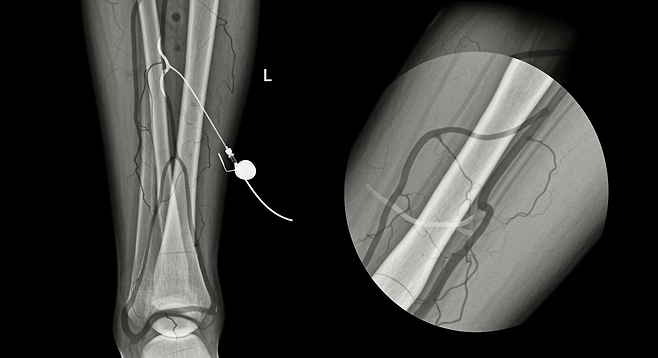

- 영상검사(CT, 혈관조영술, 혈관초음파)

- 경피적 혈관 성형술: 풍선이 달린 도관을 동맥의 협착 부위에 삽입하여 혈관을 넓히는 치료법